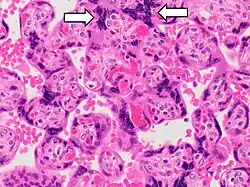

- Increased syncytial knots